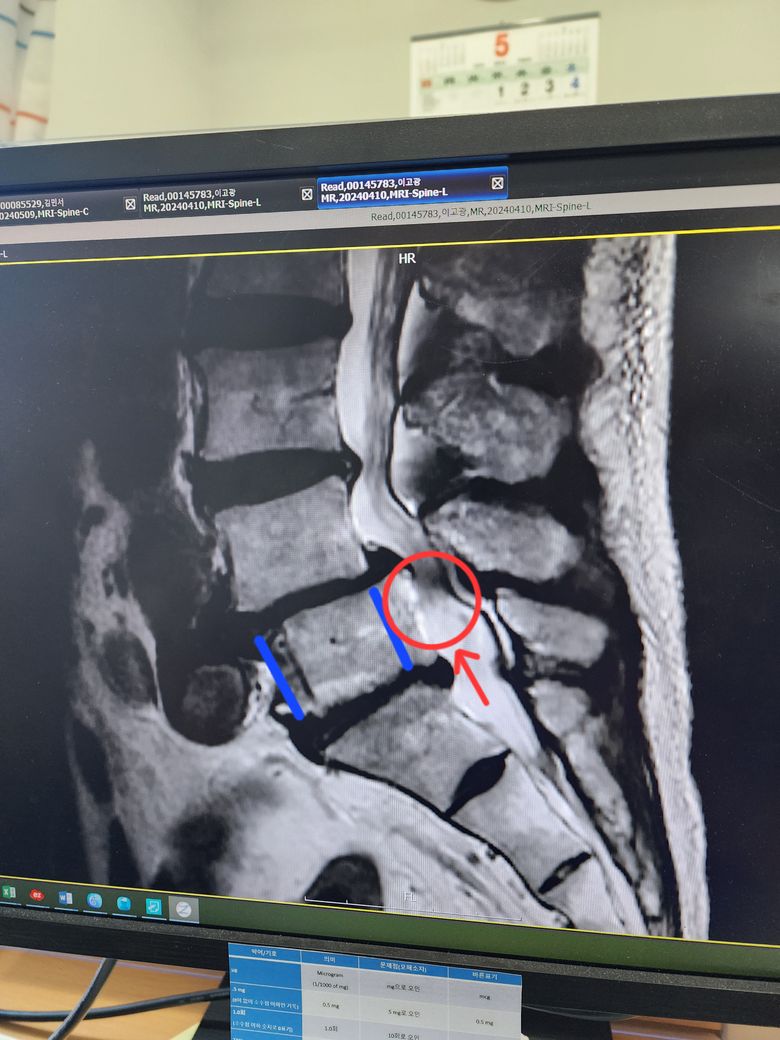

아버지께서 사진과 같이 5번 척추가 압박을 받고 있다고 하는데요

연로하신 아버지께서 다리에 힘이 잘 들어가지 않아 병원에서 CT 를 찍은 결과 5번 척추가 눌리고 있다고 하는데 나이가 있어 수술은 어렵다고 해서 한방병원을 가보니 한방병원비(약, 주사 등 3달 8백만원 정도)가 많이 나와서 안가신다고 하시는데 혹시 추나치료 만으로도 좀 좋아질 수 있을까요?